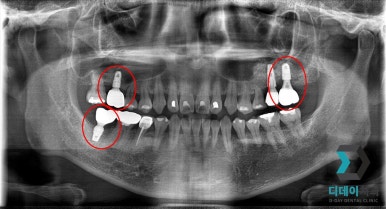

<전 2022-02-23>

<후 2022-10-14>